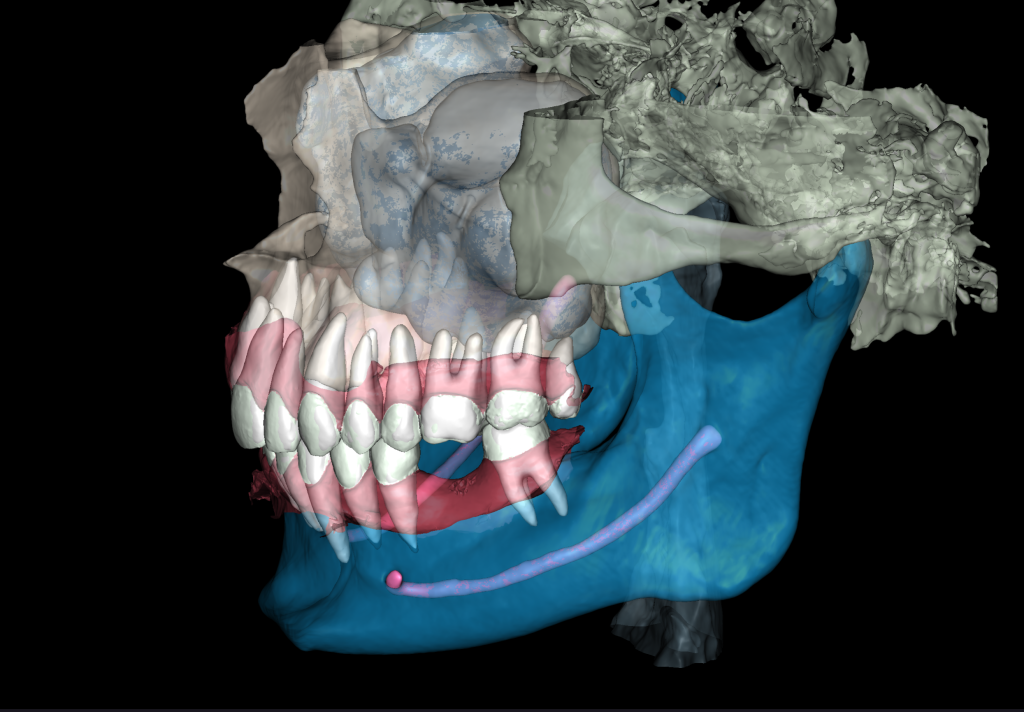

We start by loading the intraoral scan data into the Diagnocat STL module and getting a 3D model for choosing the optimal spatial position of the implant and planning the virtual design of the template for guided implant surgery

Prosthetic crown

An intraoral radiograph was uploaded into the Diagnocat FMX module, this demonstrates the most favorable prosthetic position for the implant